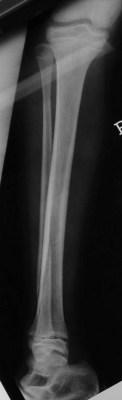

Salter 1